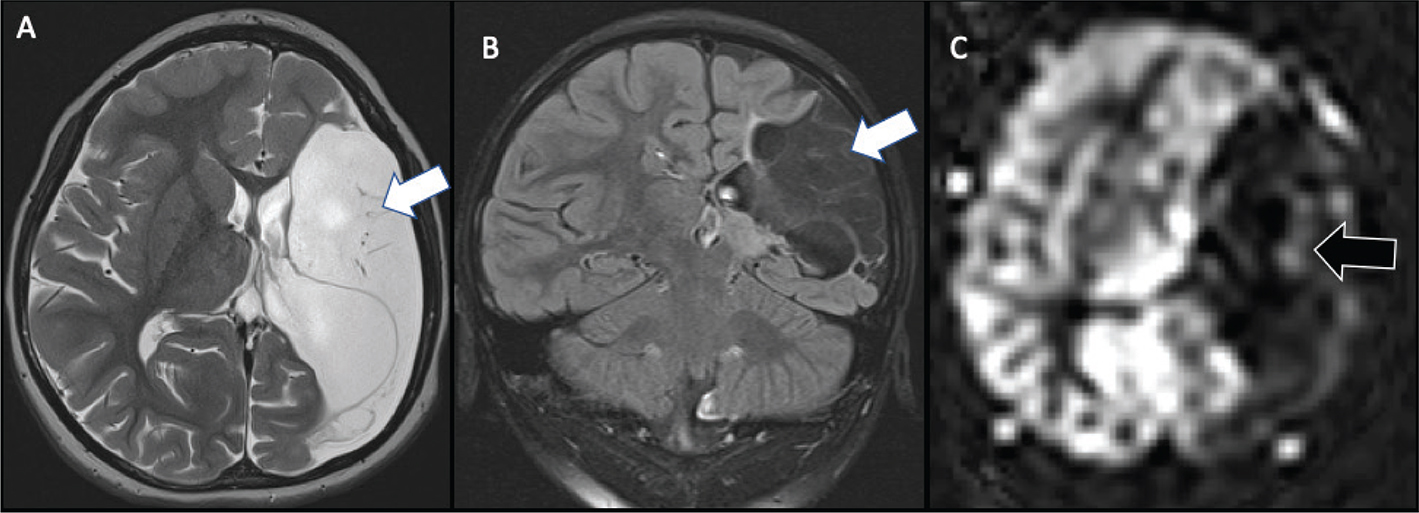

Fig 6

Figure 6. Presumed perinatal ischemic stroke (PPIS). A 10-month-old boy presented with early hand preference and medically refractory epilepsy. Axial T2-weighted (A) and coronal FLAIR (B) images demonstrate chronic infarction with liquefactive changes in the left MCA territory (white arrow) suggesting early injury, with associated decreased perfusion (black arrow) on ASL (C). Case courtesy of Dr. Tamara Feygin, Department of Radiology, Children’s Hospital of Philadelphia.